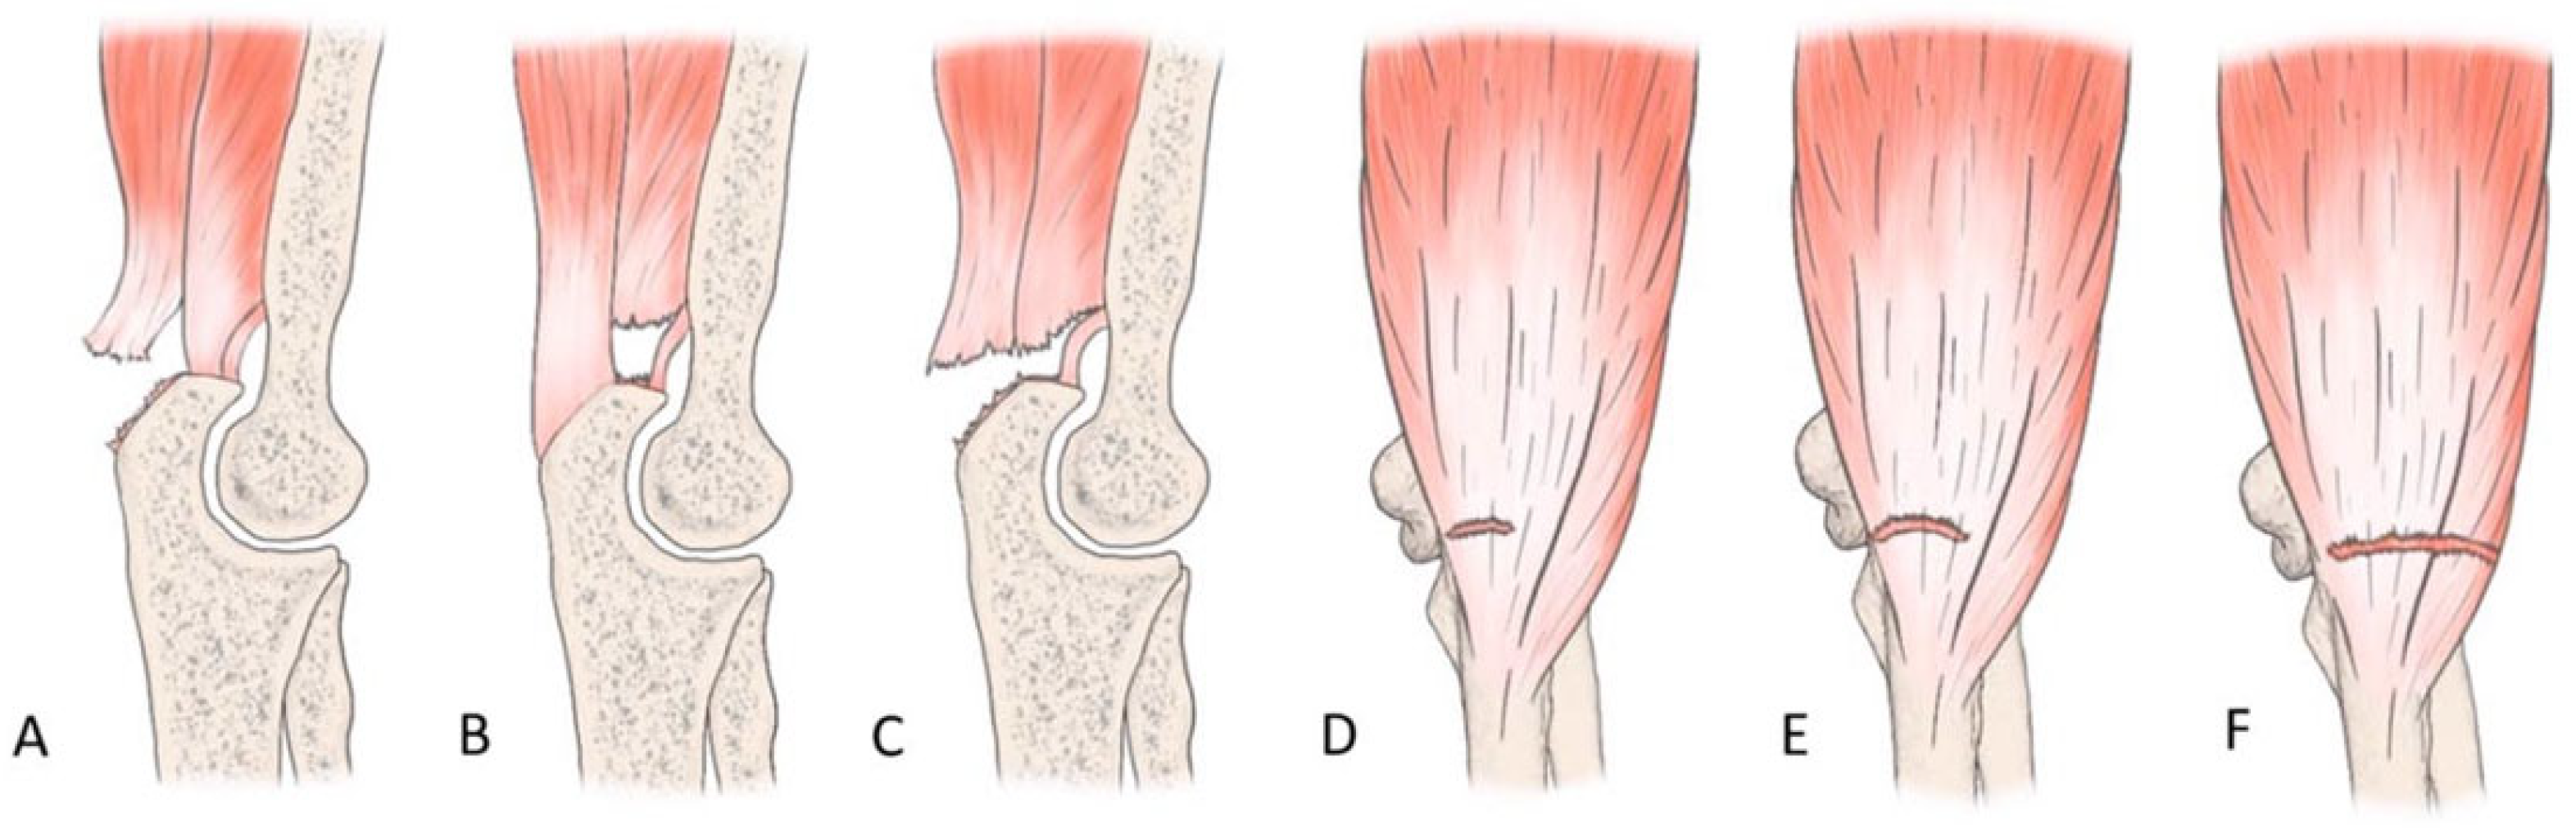

The most common tendon injuries are rotator cuff tears of the shoulder, hand flexor injuries, and achilles tendon injuries [1]. Triceps tendon rupture is the least reported among all the tendon injuries in the literature [2,3]. 65 years ago, Anzel evaluated a series of 1014 patients with tendon ruptures in various locations, and triceps tendon ruptures accounted for only 0.8% of this series [4]. Currently the prevalence is increasing, and the prevalence of triceps tendon injuries has been found to be 3.8% [5]. Theoretically, the types of tendon injuries are tendon avulsion or inside the muscle belly. In practice, a rupture almost always occurs in the area of the tendon-bone junction, and the cause is an eccentric contraction of the triceps causing a tendon deformity of more than 8% [6]. Traditionally the triceps tendon has a uniform attachment to the olecranon ulnae. This premise has caused problems in assessing the degree of damage in traumatic triceps tendon ruptures. In 2006, an anatomic study by Madsen confirmed that in most cases the medial head of the triceps has a single attachment to the olecranon ulnae [7]. This insertion is located in a deeper layer and forms a narrower part of the attachment, and very rarely is only this part damaged [8]. The long and lateral head of the triceps has a common attachment that runs more superficially, gradually extending laterally into the surrounding area towards the musculus anconeus, which helps to strengthen the bone-tendon junction. The width of the attachment correlates with the size of the olecranon and ranges from 20 to 40 mm. Paradoxically, the thickness of the tendon is not as pronounced. The attachment itself occupies a large surface area, reaching 400 mm2 in diameter and is dome-shaped [9]. These current findings are particularly important in partial tendon ruptures when a decision has to be made whether to proceed conservatively or with surgical revision. MRI is an appropriate method of choice to accurately assess the current condition. A schematic representation of the three basic types of partial DTTR rupture can be seen in Figure 1, while the normal anatomic attachment relationships of the triceps tendon in sagittal section to the olecranon ulna and a sub-complete rupture of the triceps tendon of the right hand are shown in Figure 2 and Figure 3. Furthermore, the place of attachment of the individual heads of the triceps to the olecranon ulnae is presented in Figure 4.

Figure 1. Illustration of the three basic types of DTTR partial rupture. (A): “Superficial tear”—the tendinous portion of the lateral and long head of the triceps (B): “Deep tear”—the deep muscular portion of the distal triceps involving the medial head of the triceps (C): “Full body tear”—a sub complete tear of the DTTR. (DF)—coronal planes showing partial, complete, and lateral involvement [10].